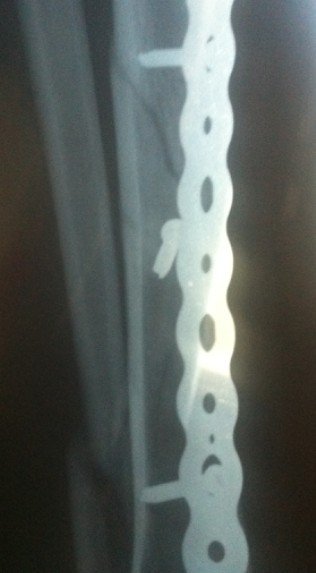

小腿胫腓骨骨折五个月啦,为什么骨折线还那么清晰,跟三个月的拍的片子差不多,这个是骨不连吗?

小腿胫腓骨骨折五个月啦,为什么骨折线还那么清晰,跟三个月的拍的片子差不多,这个是骨不连吗?不用做二次手术吧。现在我应该多下地用双拐走吗?谢谢大家啦

从片子上看,手术应该是成功的,最好能看到整体,那样就更好判抹做断一点,每个人长骨头的快慢不一样,而且即使手术成功,因为其他各种原因,骨头仍谈有不长的,现在还不是特别明确,你可能是个特例呢,是长的慢一点的那种,而且即使骨头长在一起了,骨折线很长时间还是会看到的,我的建议还是再观察几个月,尽量不要剧烈活动,还有要听给你做手术的医生的建议 ,我想现在的医生也怕你们闹的,他们的建议不凡梨碗一定是坏的,一味的责怪医生、医院那些是最不理智的做法,只会给你带来不便,给医生带来影响,恶心循环且解决不了问题。 再谈一点题外话,不要在就医过程中出现问题,就一定是医生的错,真的是医生错了,他逃避责任也逃避不了,行肆如果是正常的意外(包括一些并发症:术后感染、骨折不愈合,骨折愈合缓慢等等,都是正常存在的,几率虽小,在你身上发生就是100% ),请大家多一份理解, 要积极配合医生把并发症产生的后果讲到最低。